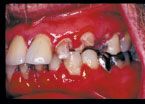

It is well known in the dental community that the emergence of the HIV infection in the early 1980s was accompanied by an explosion of some common and some rarer oral conditions including candida infections, Kaposi’s sarcoma, hairy leukoplakia, and a variety of other bacterial infections. In addition, HIV-associated infections associated with the periodontium included a linear gingival erythema (Fig. 3), necrotizing gingivitis (Fig. 4), human papilloma virus, and most seriously a necrotizing periodontitis with both soft- and hard-tissue necrosis that could extend beyond the periodontal tissues (Figs. 5-7).